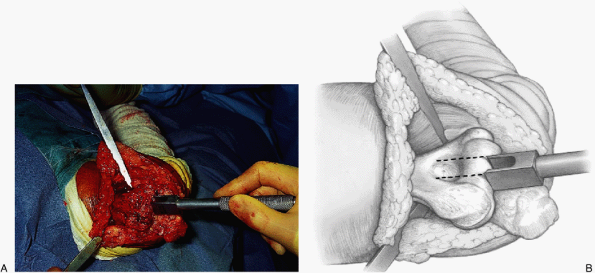

of soft tissue. A hole is made in the base of the coronoid to gain

access to the ulnar intramedullary canal, and a trough from the

coronoid through the olecranon is developed (Fig. 17-11). An intramedullary rod and cutting

jig are applied and the articulated surface is removed using an

oscillating saw. A power bur is used for final modifications. It is

![]() |

|

Figure 17-11. A,B:

The triceps fascial sleeve is grasped to secure the ulna, and the medullary canal is identified with a bur at the base of the olecranon. |